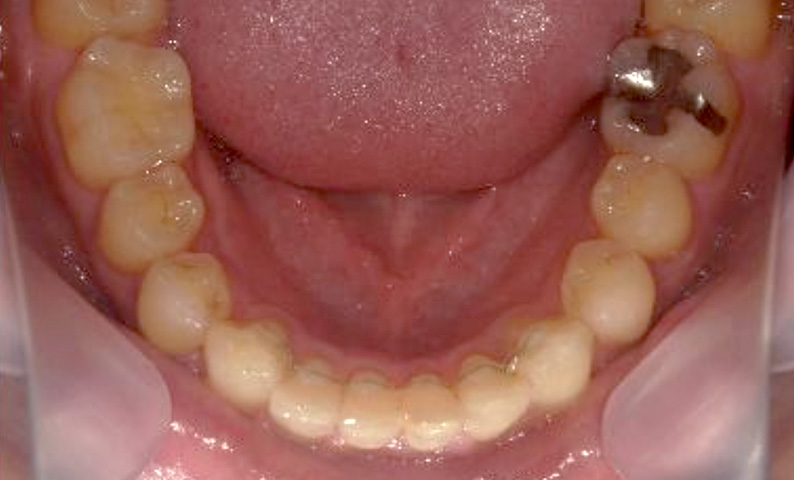

症例_003 下顎だけの部分矯正

治療期間:10ヶ月金額:24万円+税女性前歯のガタガタ下の前歯だけ上顎は補綴治療中

| Before | After |